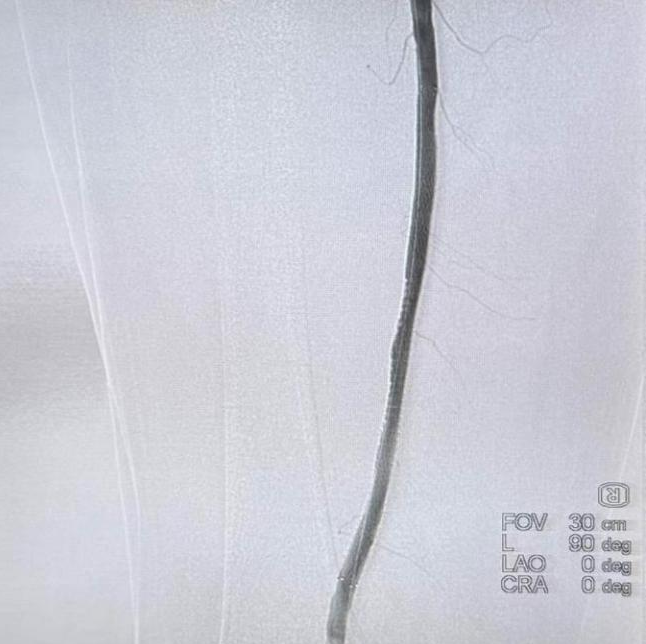

在血栓负荷基本清除后,团队进一步行球囊扩张及支架植入术处理狭窄的血管基础病变。术后即刻造影显示,股浅动脉及腘动脉血流通畅,远端胫后动脉及腓动脉显影良好。

术后血流通畅

郑大爷冰凉发紫的右脚在手术台上随即逐渐转暖,剧烈疼痛迅速消失,术后患肢成功保住!目前恢复情况良好,郑大爷和孩子感激不尽。